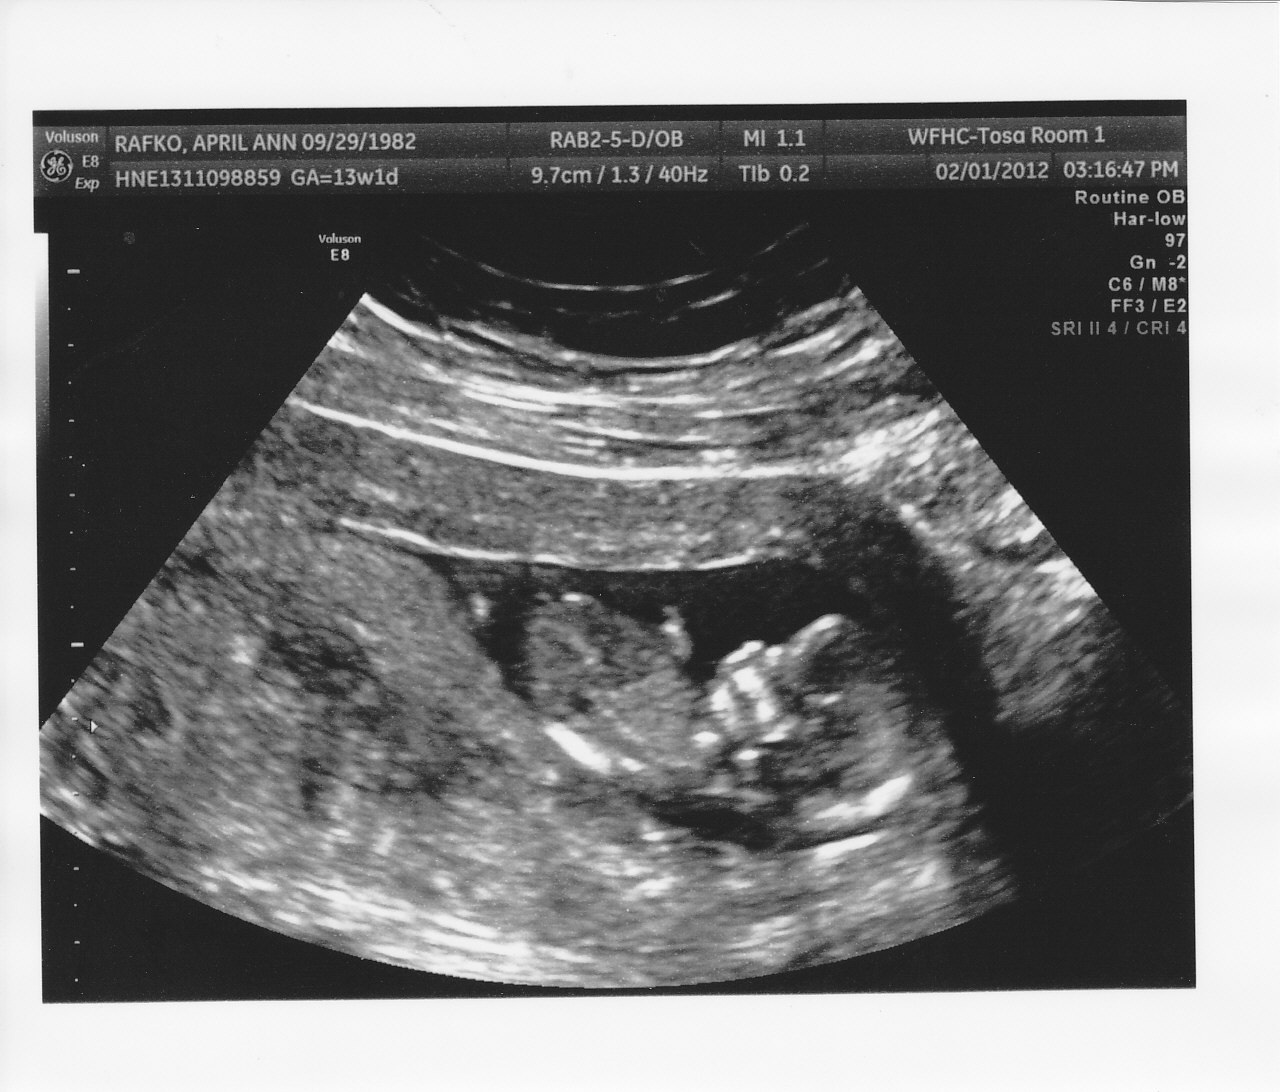

Here are two more photos from the same u/s...do either of these help?

I *thought* in the first pic it could go either way, but the 2nd pic looks girlie to me, so I'm guessing girl. Good luck.

Now I think maybe girl LOL!

I'm thinking girl too, good luck! keep us updated.

So according to the skull theory does this look like a boy or girl? I was trying to figure it out but I'm really new. In some I really thought girl because it seems rounded. Am looking at it correctly?

I think the skull looks girly. GL!!!